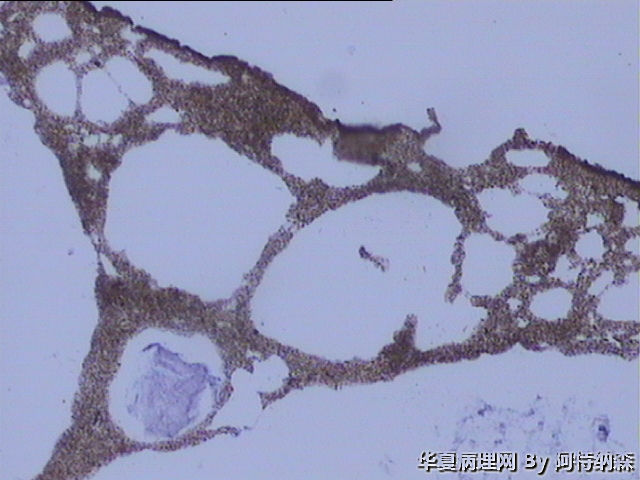

女.61岁,小便时掉出不明物4天。间断尿道刺激症状3年。绝经10年。未同房3年。

病人诉述为尿道流出物,因是小便时掉出来的,小便时下身比较痛,B超提示膀胱炎症。尿潜血阳性。妇科检查未见异常。

组织大小8x8x2cm,似蘑菇,柔软,大体有点像肺组织,颜色和柔软度也很像。有握雪感,脱水前后性状无变化。脱水程序对组织好像不起作用。切片不好切,新刀片就出现很多细微的划痕。

镜下未见任何细胞成分,只有蜂窝状结构,高倍下由细微的沙粒样物组成。蜂窝腔内可见蓝染的粘液样物。

无组织学结构,只是蜂窝状结构,没有细胞成分。